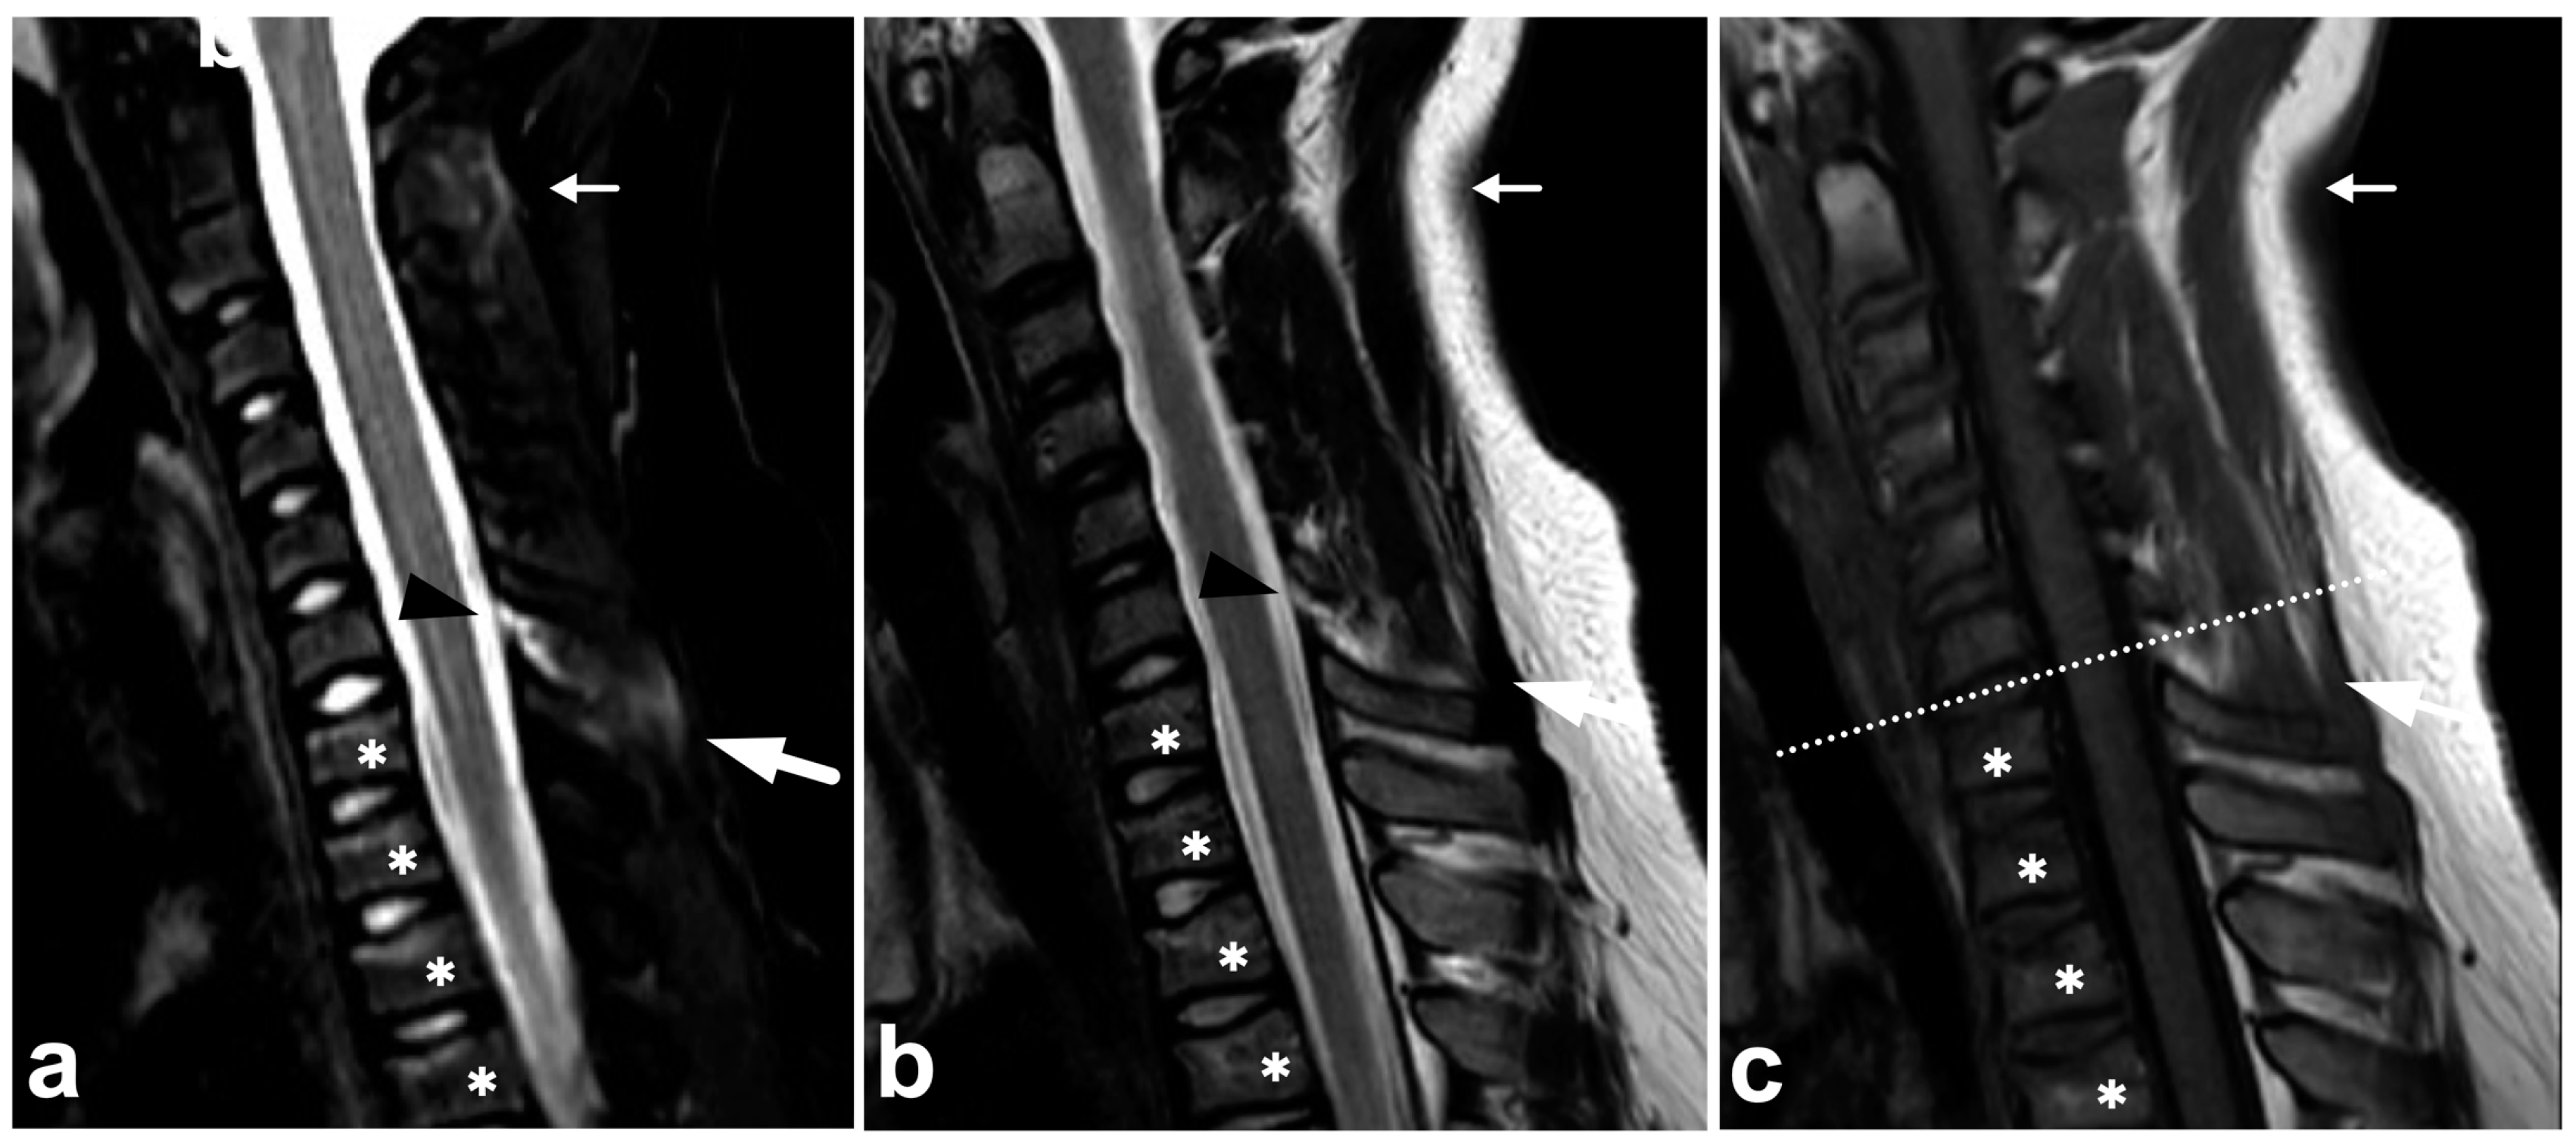

4.2. Posterior Ligament Complex

4.3. Anterior and Posterior Longitudinal Ligaments